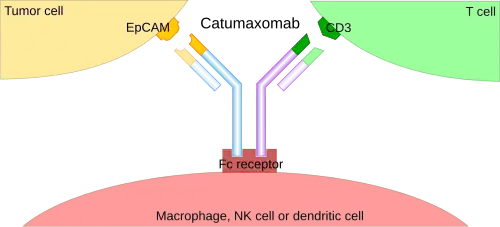

This format retains the traditional monoclonal antibody (mAb) structure of two Fab arms and one Fc region, except the two Fab sites bind different antigens. The most common types are called trifunctional antibodies, as they have three unique binding sites on the antibody: the two Fab regions, and the Fc region. Each heavy and light chain pair is from a unique mAb. The Fc region made from the two heavy chains forms the third binding site. These BsAbs are often manufactured with the quadroma, or the hybrid hybridoma, method.[12][13][14]

The binding of a BsAb to its target antigens can lead to a variety of effects. The most widely used application of this approach is in cancer immunotherapy, where BsAbs are engineered to simultaneously bind a cytotoxic cell and a target (a tumour cell) to be destroyed. It is possible to observe the bridging effect that BsAbs have on T cell/cancer cell interactions using label-free live cell imaging. Catumaxomab, one of the first trifunctional antibodies approved for therapeutic use, binds both CD3 on cytotoxic T cells and EpCAM on human adenocarcinomas.[12][13] The Fc region additionally binds to a cell that expresses Fc receptors, like a macrophage, natural killer cell or dendritic cell. Since the Fc region is still intact, this allows for the BsAb to trigger common immune responses when recognized by an Fc receptor, such as antibody-dependent cell-mediated cytotoxicity or complement-dependent cytotoxicity.[14][16]

Several bispecific antibodies are presently in clinical use. Blinatumomab, which targets CD19 and CD3, is used in the treatment of Philadelphia chromosome negative B cell acute lymphoblastic leukemia (ALL). Emicizumab, which targets clotting factors IXa and X, is used in the treatment of hemophilia A.[34] Catumaxomab was withdrawn from the European market in 2017 for commercial reasons.[35] Amivantamab, which targets epidermal growth factor (EGF) and MET receptors, for adult patients with locally advanced or metastatic non-small cell lung cancer (NSCLC) with epidermal growth factor receptor (EGFR) exon 20 insertion mutations.[36] Teclistamab, which targets CD3 and B-cell maturation antigen (BCMA), is used in the treatment of multiple myeloma,[37] and zenocutuzumab.